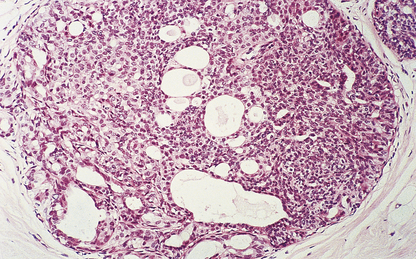

Medullary carcinomas are circumscribed and often large. Histologically, they are composed of large tracts of confluent cells with little stroma in between them. The cells show quite marked nuclear pleomorphism, and mitotic figures are frequent. There is never evidence of gland formation. These cytological appearances put them into the ‘poorly differentiated’ category. Around the islands of tumour cells there is a prominent lymphocytic infiltrate, predominantly T-lymphocytes, with macrophages (Fig. 18.26).

image

Fig. 18.26 Medullary carcinoma. Large groups of irregularly shaped tumour cells are surrounded by an infiltrate of lymphocytes.

Despite the aggressive cytological features of these tumours, the patients have a significantly better 10-year survival than women with invasive duct carcinomas. It may be that the lymphocytic and macrophage infiltrate has a beneficial effect, and this has stimulated much research into the immunological responses to tumours generally.